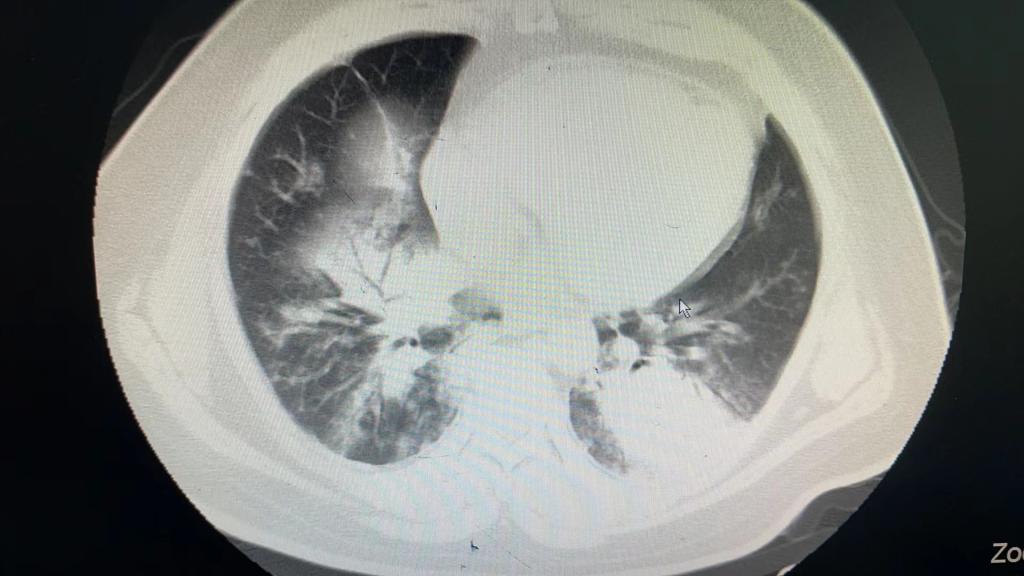

患者以“发热6天伴呼吸衰竭”从外院转入我院EICU,CT呈“白肺”样改变,入院后气管插管呼吸机辅助通气,氧浓度100%,血氧饱和度不到80%,氧合指数只有50,生命岌岌可危。千钧一发之际,ECMO团队迅速全面的病情评估后,紧急启用ECMO支持治疗。

图1 图2腺病毒感染的白肺